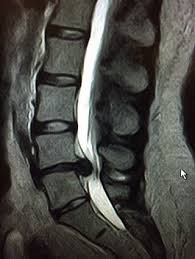

Ernia del Disco Lombare

Cos’è

L’ernia del disco si verifica quando il materiale interno del disco intervertebrale (nucleo polposo) fuoriesce attraverso una fessura dell’anello esterno (anulus fibroso).

Questa fuoriuscita può comprimere le radici nervose, causando:

- Dolore acuto e irradiato lungo la gamba (sciatica)

- Formicolii o intorpidimento

- Debolezza muscolare